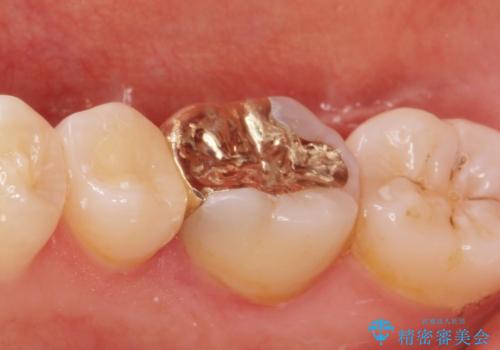

- 過去の樹脂の治療の劣化を治したいとの事で来院。大臼歯の歯は樹脂の範囲が大きくセラミックインレーで処置しても割れてしまう可能性があるため被せ物のご案内をしたところ、なるべく歯を削りたくないとのことでPGAアンレー(ゴールドアンレー)での治療となりました。手前の歯はセラミックの詰め物で治療する事ができました。

- e-maxインレー 7.7万円 PGAアンレー 11万円費用は治療当時の料金となります

歯質の削除量をなるべく最小限にして治療が終わりました。

セラミック、ゴールド共に適合が良く虫歯の再発のリスクが低くなります。